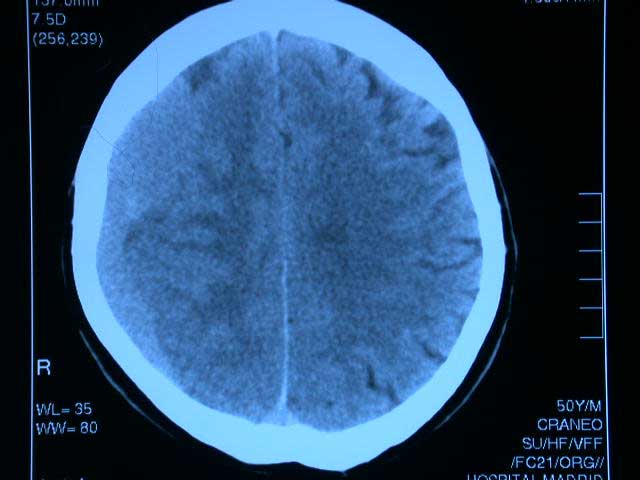

Triple terapia antiagregante plaquetaria con aspirina, clopidogrel y dipiridamol frente a clopidogrel, aspirina o dipiridamol solos en pacientes con isquemia cerebral aguda (TARDIS): ensayo de superioridad de fase 3 aleatorizado y abierto

Lancet, 20 de diciembre de 2017 Después de 3096 pacientes asignados aleatoriamente (más del 70% del tamaño de muestra objetivo de 4200 pacientes), el comité de control de datos recomendó que se detuviera el ensayo por futilidad (para el criterio de valoración primario y debido a un mayor riesgo de hemorragia, en particular hemorragia fatal, en el grupo de terapia intensiva En pacientes con isquemia cerebral reciente, el tratamiento antiagregante plaquetario intensivo (triple terapia) no reduce la incidencia ni la gravedad de los accidentes cerebrovasculares recurrentes o el AIT, pero sí aumenta significativamente el riesgo de hemorragia mayor. La triple terapia antiplaquetaria no debe usarse en la práctica clínica habitual.